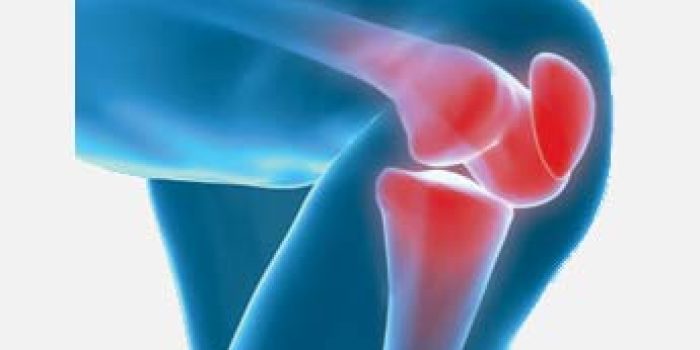

استئوآرتریت یا سائیدگی زانو که به آن آرتروز زانو هم می گویند از شایعترین علل درد زانو در سنین متوسط و بالا است که در آن غضروف مفصل دچار آسیب می شود. این بیماری صرف نظر از درد و تورم موجب تغییر شکل و اشکال در راه رفتن هم می شود.

درد مفصل بتدریج افزایش می یابد و پس از فعالیت غیرعادی بدتر می باشد . حرکات زانو تا حدودی محدود شده و با صدایی شبیه خرد شدن همراه هستند . در موارد شدید بیماری زانو خم شده و تغییر شکل بصورت دور یا نزدیک شدن زانوها از هم دیگر ایجاد می شود .